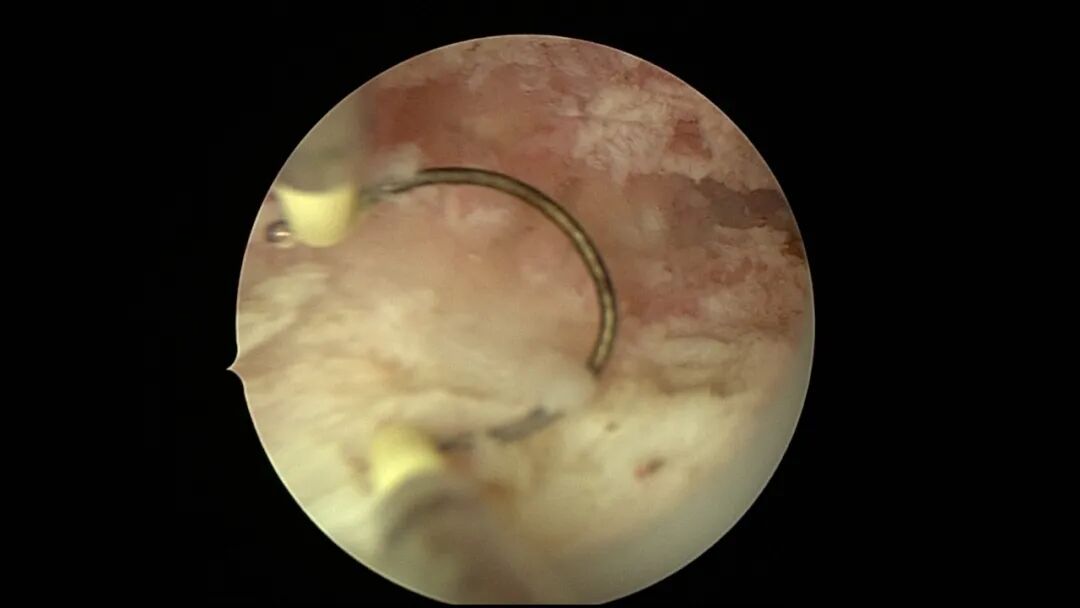

第八次宫腔镜:2025年7月宫腔镜二探取球囊,宫腔形态正常,双侧输卵管开口可见,内膜薄,片状充血。球囊在宫腔具有持续塑形作用,分粘术中没有显露的右侧输卵管开口已自我修复。